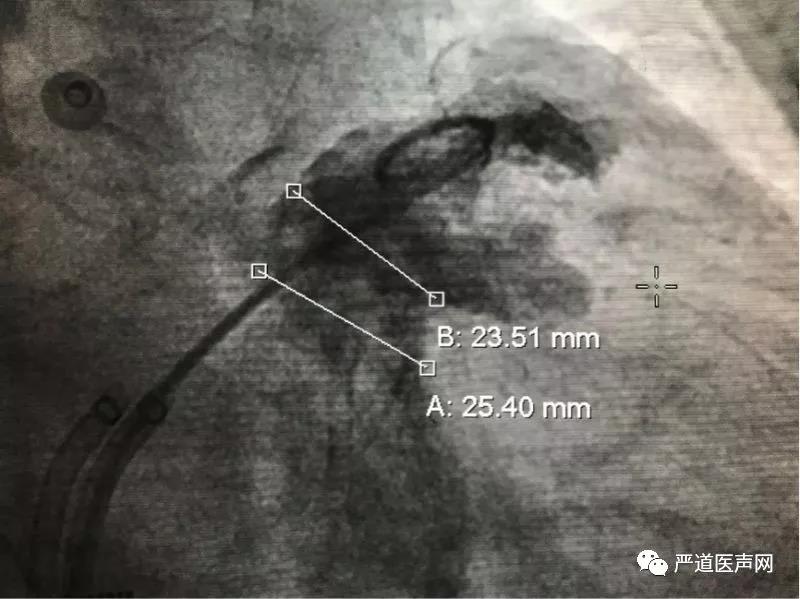

此次接受手术的是位71岁的男性患者,因反复胸痛10余年,心悸8年而入院寻求治疗,被诊断为心律失常持续性心房颤动,合并冠状动脉粥样硬化性心脏病,高血压病3级极高危组,陈旧性心肌梗死等其他病种,CHA2DS2-VASC=3,HAS-HLED=3,符合房颤消融及左心耳封堵适应症,循例对其施行房颤消融联合左心耳封堵手术。当日,在射频消融双侧肺静脉隔离完成后,置入猪尾导管进行左心耳造影,测量左心耳固定盘参考线为23.5mm,密封盘参考线为25.4mm,选用LAmbre™2632封堵器成功封堵,造影验证符合LAmbre™ COST释放原则后释放封堵器。释放后造影提示封堵完全,无残余分流;且在经食道超声0°,45°,90°,135°切面提示封堵完全,对二尖瓣及左上肺静脉结构功能无影响。

左心耳造影测量